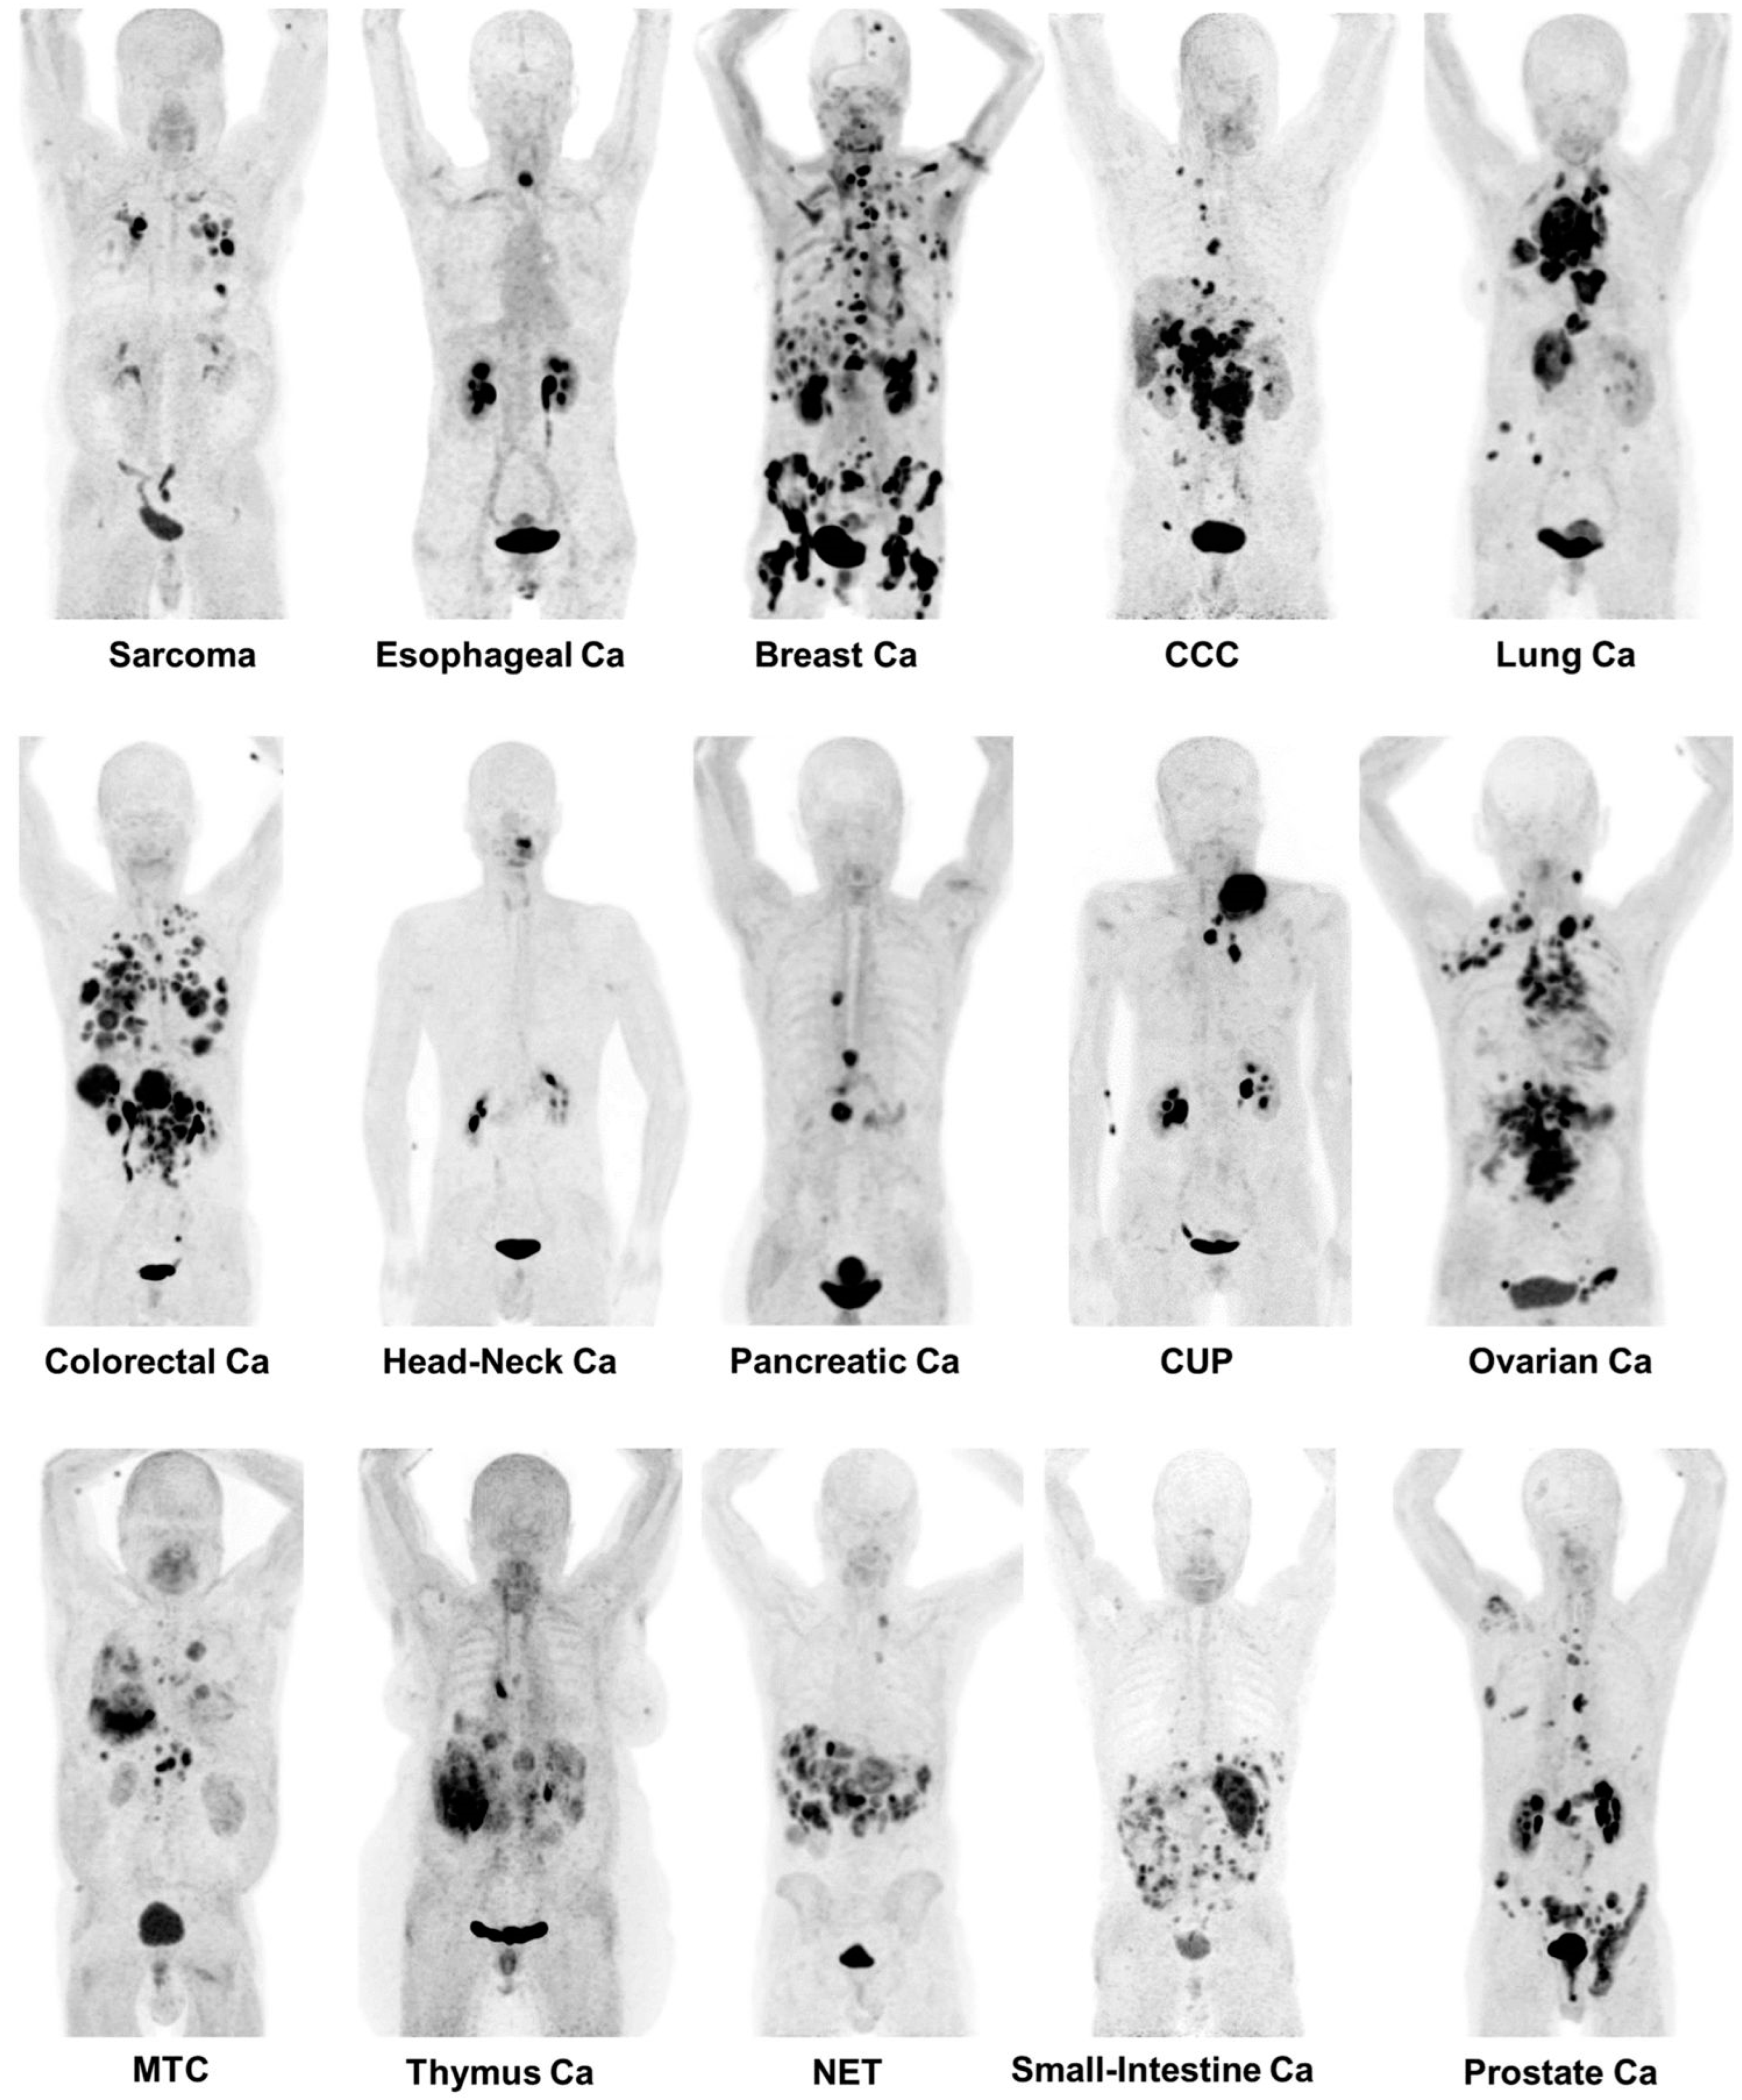

- Kratochwil, C.; Flechsig, P.; Lindner, T.; Abderrahim, L.; Altmann, A.; Mier, W.; Adeberg, S.; Rathke, H.; Röhrich, M.; Winter, H.; et al. 68Ga-FAPI PET/CT: Tracer Uptake in 28 Different Kinds of Cancer. J. Nucl. Med. Off. Publ. Soc. Nucl. Med. 2019, 60, 801–805. [Google Scholar] [CrossRef] [PubMed]